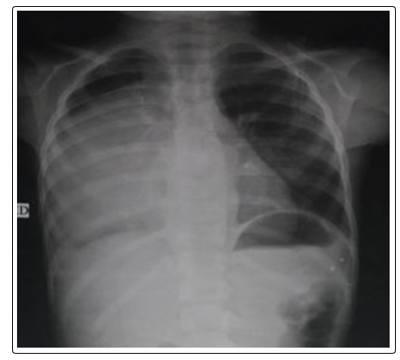

Female child 8-years old presented with her mother to the outpatient clinic of the pediatric department at Abbasis Pulmonary Hospital, Cairo governorate, Egypt. The child was complaining of repeated right sided chest pain .The pain started 4 months before presentation to our hospital, the pain is sharp in character and mild in intensity. The pain was affecting the lower part of the right chest, and sometimes referred to the upper abdomen. The pain is on and off in character and each times lasts about one minute or two. The pain had no aggravating or relieving factors. There was no history fever, weight loss no GIT symptoms or other respiratory symptoms. The history of the pregnancy given by her mother was normal with vaginal delivery. Also, all the child developmental milestones were normal. Family history and consanguinity were negative. A plain chest X-ray P-A view was done in the outpatient clinic that revealed a huge well circumscribed, radio opaque, homogenous posterior mediastinal mass (Figure 1). So the child was admitted to the pediatric department for further evaluation.

Figure 1: Chest X-ray P-A view showing:

Giant opacity occupying most of the right hemithorax